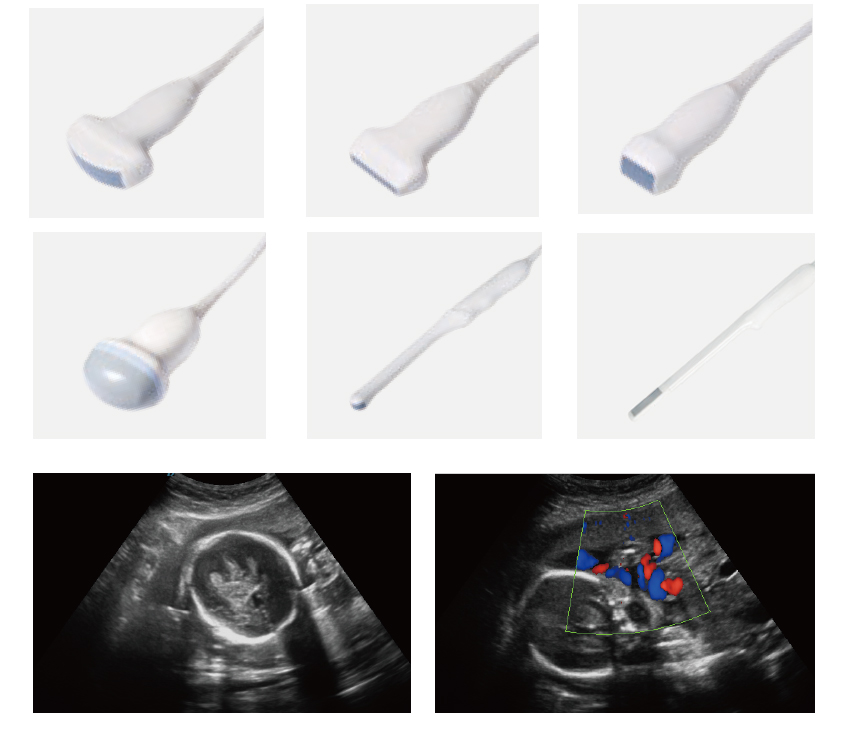

Platformă ecografică cu suport multi-sondă

Sistemul ecografic permite integrarea unei game extinse de sonde dedicate, bazate pe tehnologie avansată array și sub-array de înaltă densitate.

Arhitectura transductorilor optimizează transmiterea și recepția semnalului ultrasonic, asigurând rezoluție spațială superioară, penetrare adecvată în profunzime și fidelitate ridicată a detaliilor anatomice.

Configurarea modulară a sistemului permite adaptarea rapidă la diferite aplicații clinice, susținând performanța diagnostică în multiple specialități.

Sistemul suportă o gamă completă de transductori pentru aplicații abdominale, obstetricale, ginecologice, cardiologice, vasculare și musculo-scheletale.

Include sondă convexă, liniară, phased array, volumetrică 4D, transvaginală și transrectală, asigurând rezoluție ridicată, penetrare optimă și performanță diagnostică adaptată fiecărei specialități.